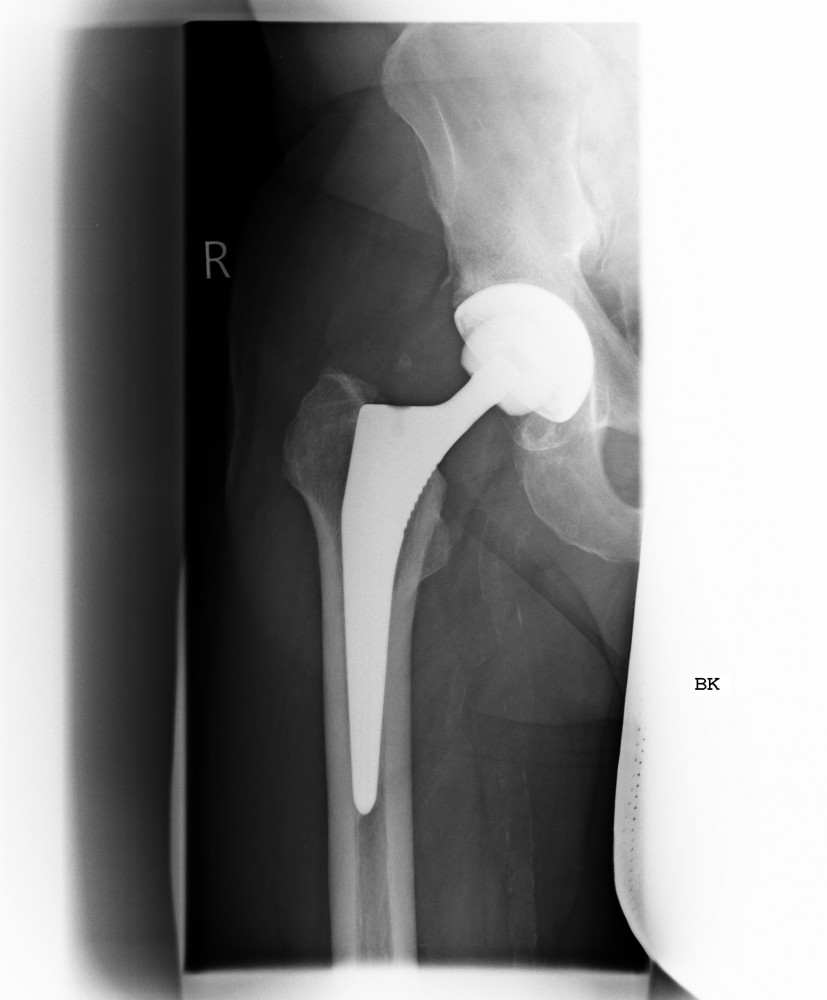

Kurzschaftprothese

Ziel einer Endoprothese ist es bei der Implantation möglichst viel Knochen zu erhalten. Somit wurden in den letzten Jahrzehnten Prothesenmodelle entwickelt, die aufgrund Ihres Designs eine optimale Krafteinleitung in den Knochen bei maximalen Knochenerhalt gewährleisten. Bei diesen sogenannten Kurzschaftprothesen wird außerdem die Biomechanik des Gelenkes kaum verändert. Dies hat zur Folge dass Sie das Implantat kaum noch bis gar nicht „spüren“.